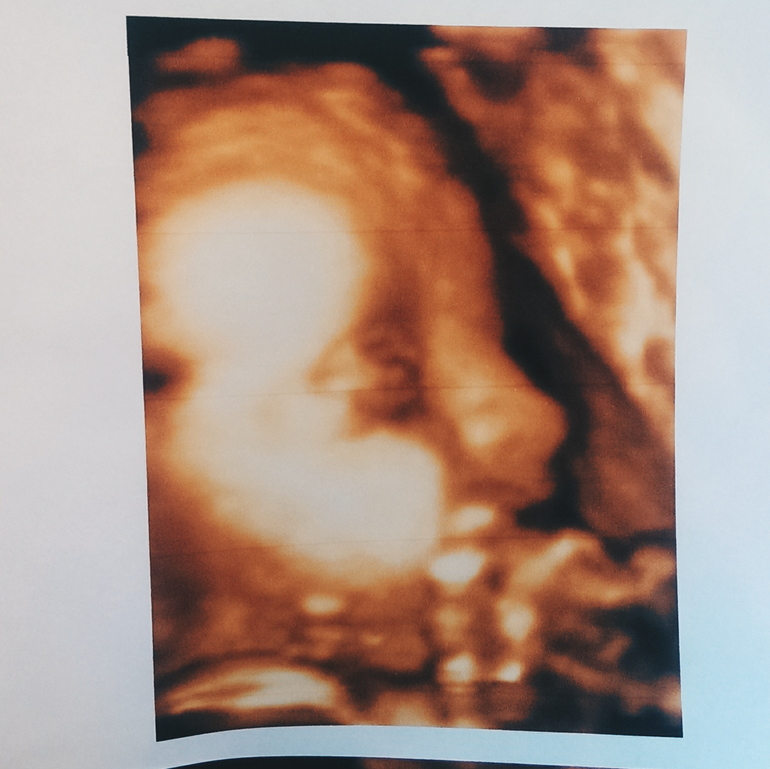

Резус-фактор / Резус-конфликтПозвонила в тот день, когда узнала резус фактор малышки, своему врачу. Она говорит во вторник будет ровно 28 недель я выпишу направление на укол бесплатно, типа даже не парься. Выписала, пошла я с этим направлением в роддом, сказали приди завтра с результатом нового узи, мочой и натощак ) думаю ладно. Пошла сходила на узи платно , с малявочкой моей все хорошо )) растем ) весит 1340 😳